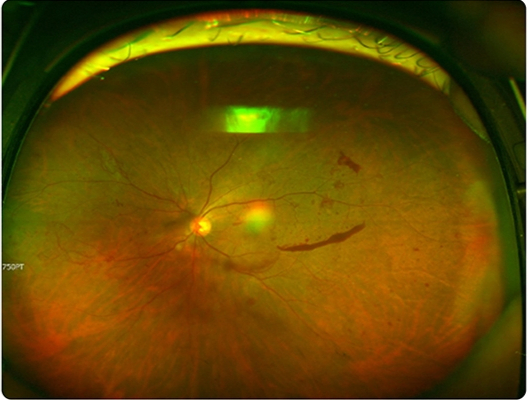

망막은 눈의 가장 안쪽에서 빛을 감지하고 시각 정보를 뇌로 전달하는 신경조직으로, 이 부위에 손상이 생기면 중심 시야가 흐려지거나 시야 일부가 가려지는 등 심한 경우 실명으로 이어질 수 있다.

대표 질환으로는 △당뇨망막병증 △망막박리 △망막혈관폐쇄 △황반변성 등이 있다. 초기 자각 증상이 거의 없어 병이 상당히 진행된 뒤에 발견되는 경우가 많아 주의가 필요하다. 강동경희대병원 안과 김유진 교수의 도움말로, 망막질환의 증상과 치료법에 대해 알아본다.

이런 망막 질환은 △세극등 안저 검사 △망막안저촬영 △빛간섭단층촬영(OCT) 등을 통해 진단한다. 필요하면 형광안저혈관조영술(FAG)과 빛간섭단층촬영 혈관조영술(OCTA)을 통해 신생혈관 발생이나 혈관 누출과 폐쇄 여부를 평가할 수 있다.